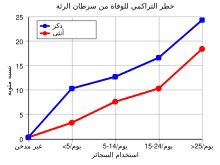

عوامل الخطر

⚠️ من يكون معرض أكثر للخطر؟

1️⃣ المدخن اليومي 🚬

2️⃣ المعرض للتلوث 🏭

3️⃣ من لديه تاريخ عائلي 👥

الخطر يتراكم... احذر! x.com

⚠️ من يكون معرض أكثر للخطر؟

1️⃣ المدخن اليومي 🚬

2️⃣ المعرض للتلوث 🏭

3️⃣ من لديه تاريخ عائلي 👥

الخطر يتراكم... احذر! x.com